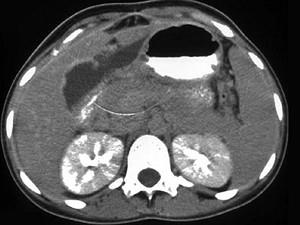

问题 女,45岁,急性右上腹剧痛2小时,向右肩放射,影像检查如图,应诊断为 ( )

选项 A、胆囊腺肌增生症 B、胆道梗阻 C、慢性胆囊炎 D、胆囊穿孔 E、急性胆囊炎 单选题

答案 D